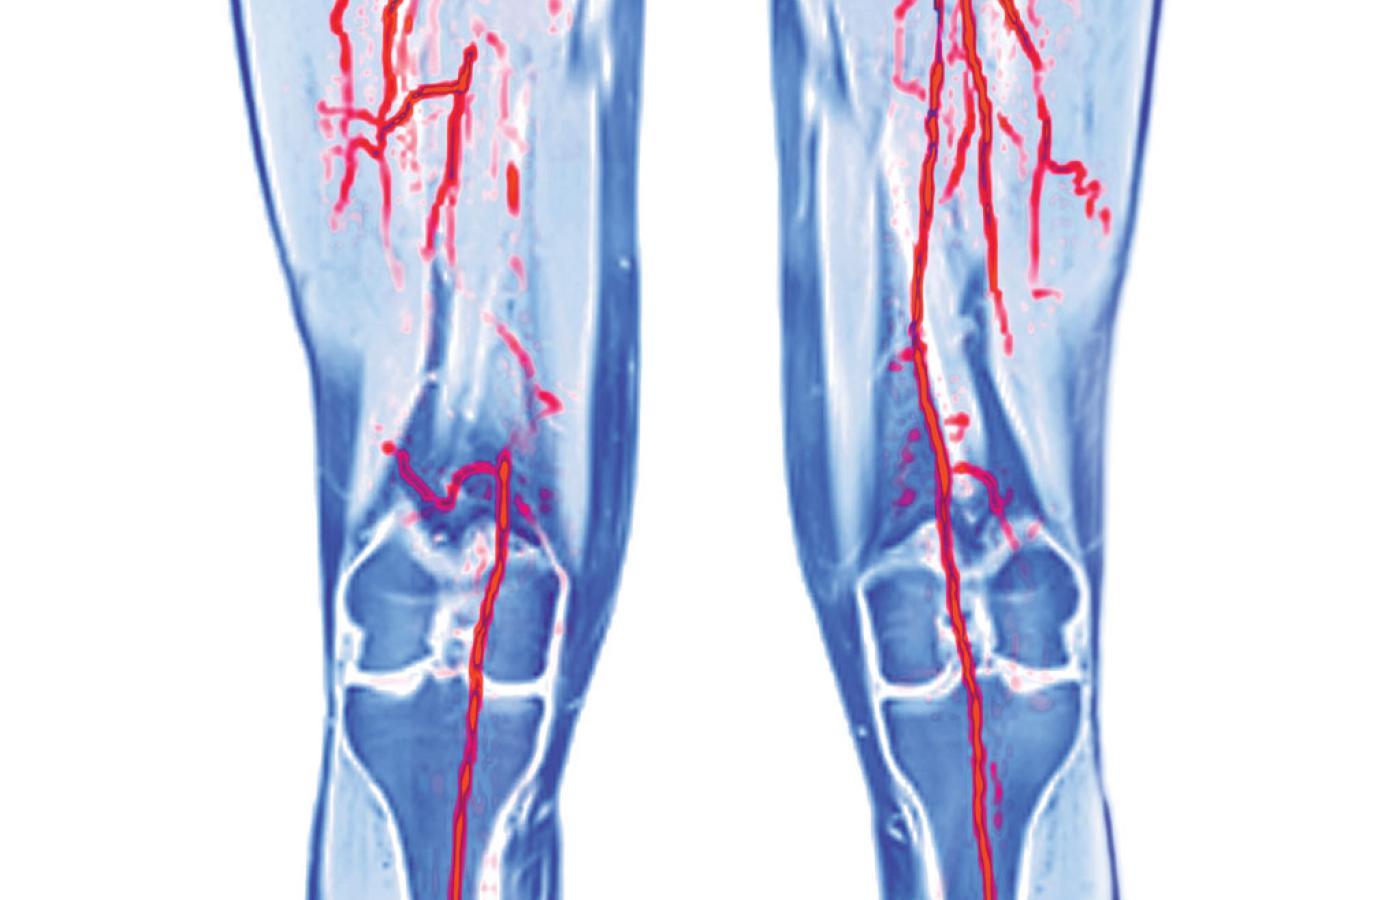

Zakrzepica kończyn dolnych widoczna w rezonansie magnetycznym.Science Photo Library Zakrzepica kończyn dolnych widoczna w rezonansie magnetycznym.